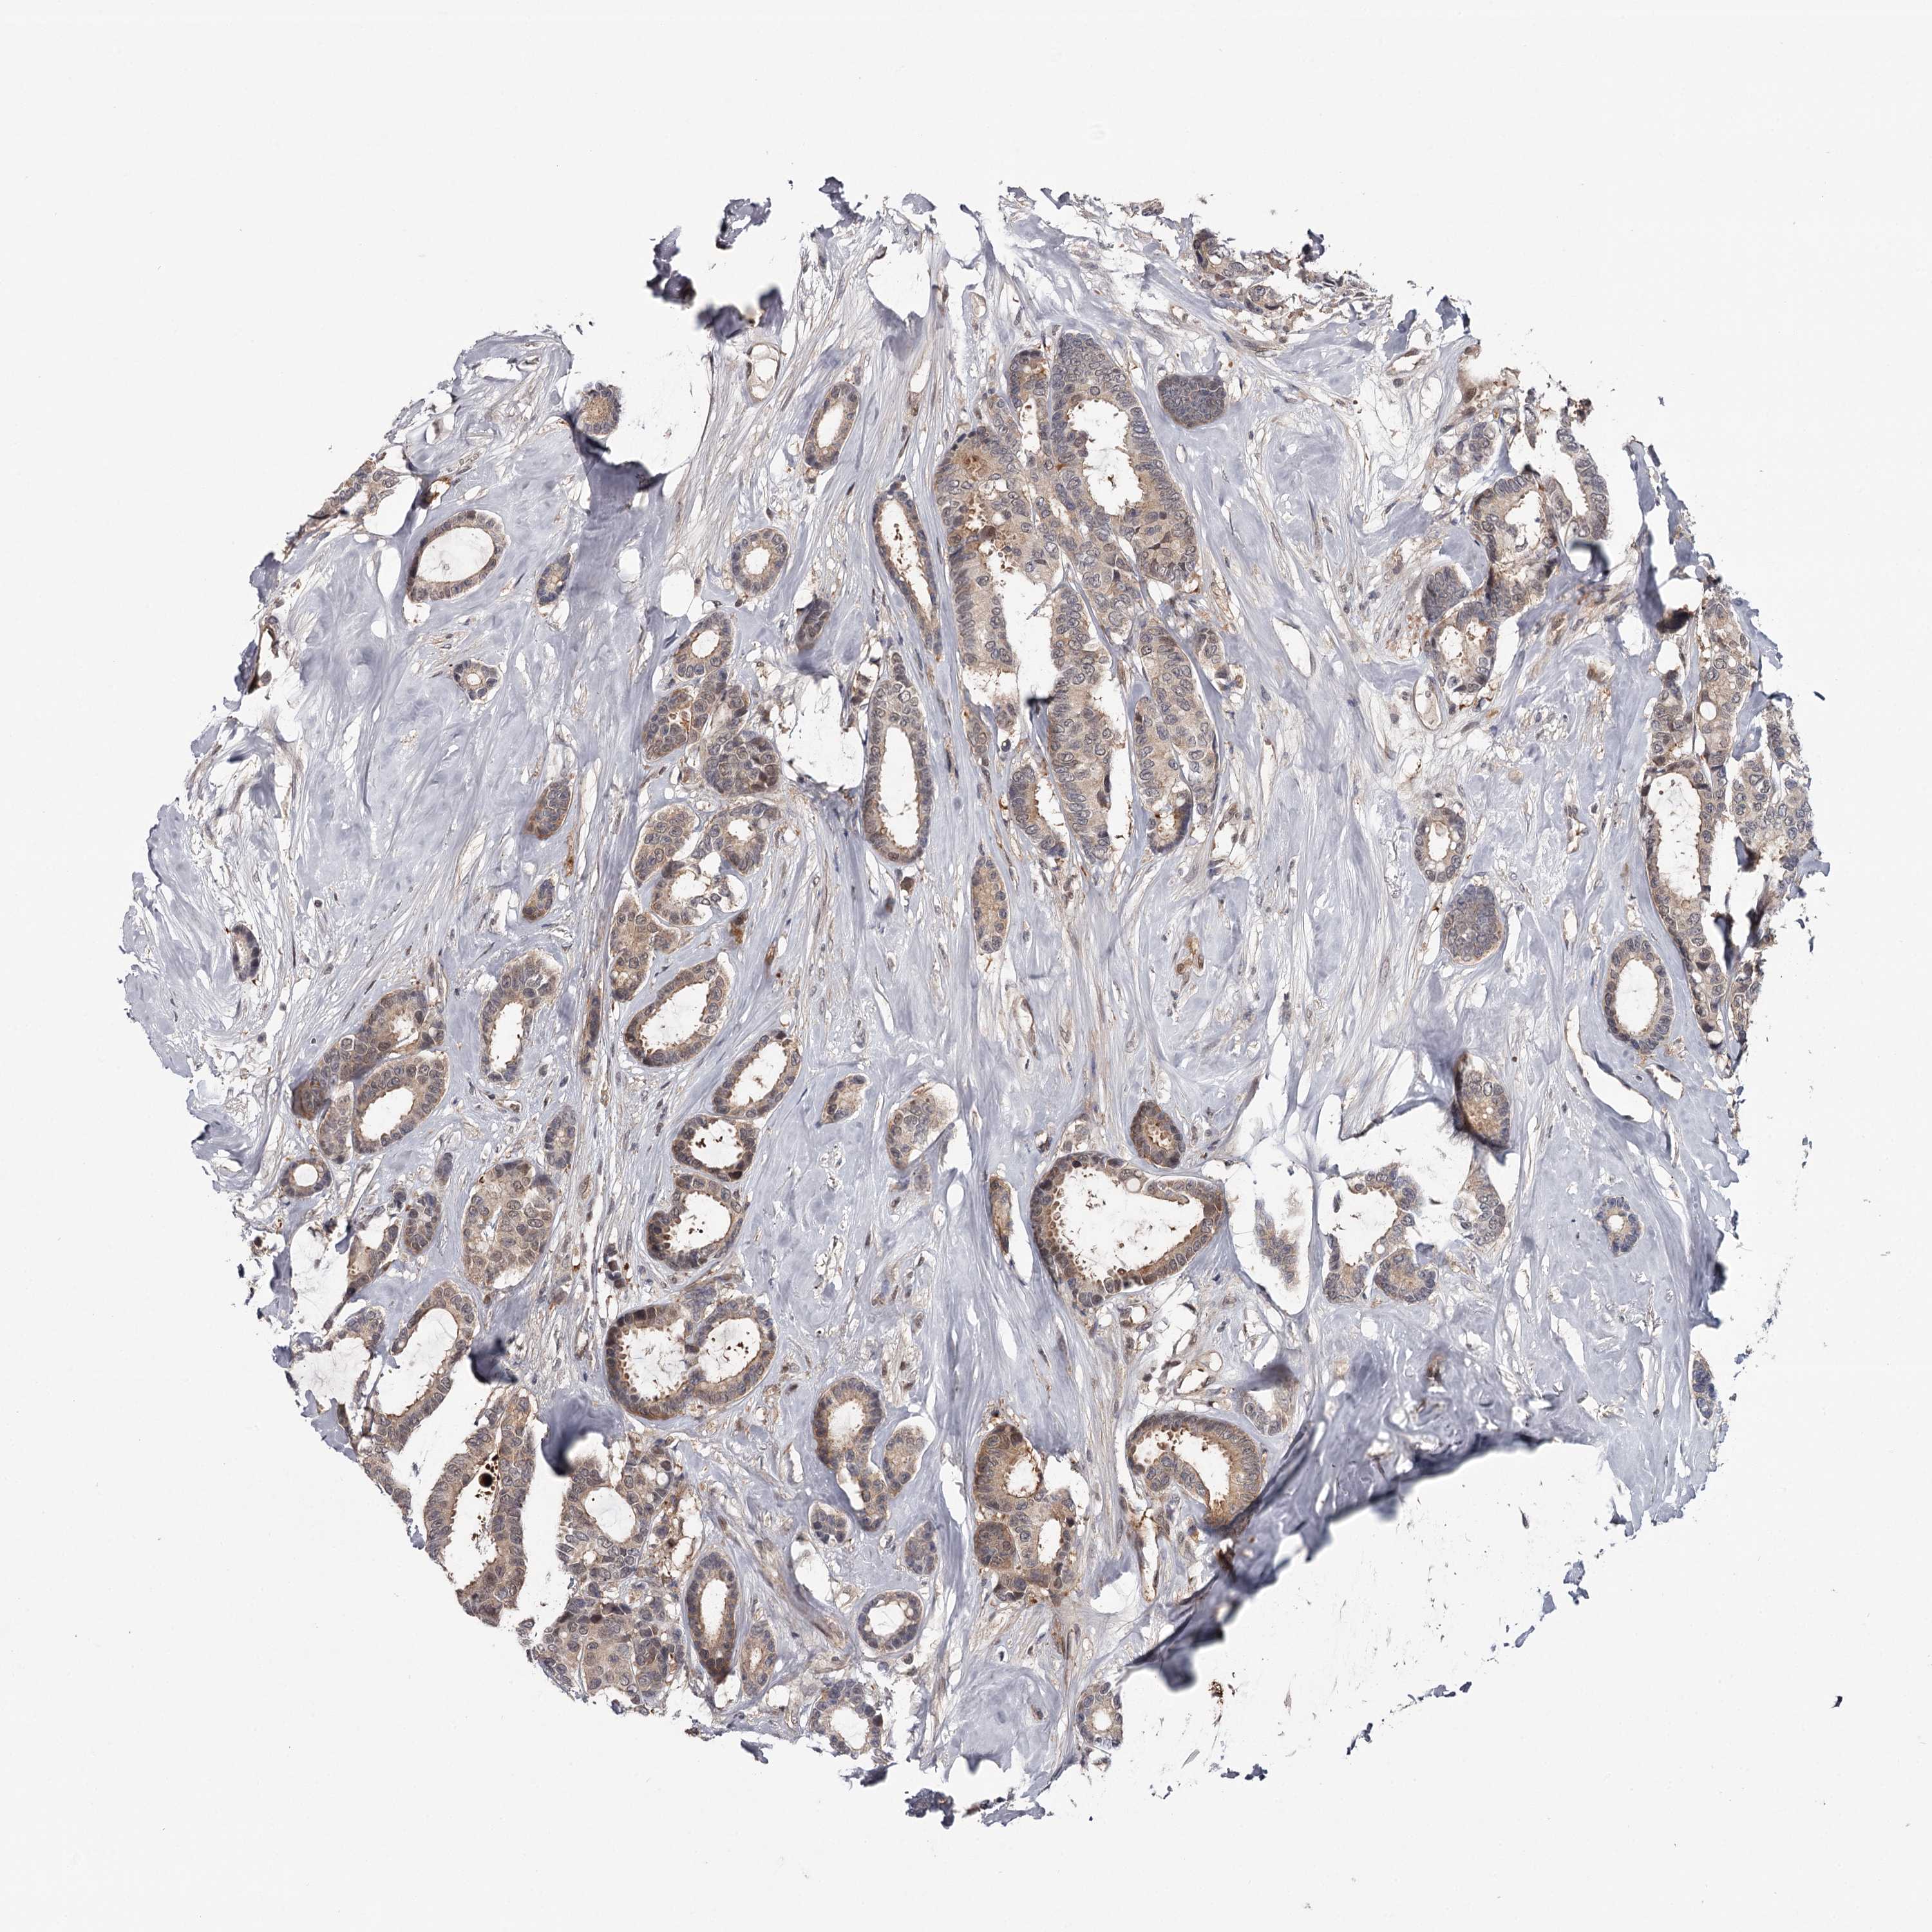

BRCA TCGA BRCA VALIDATION PROTEIN EXPRESSION